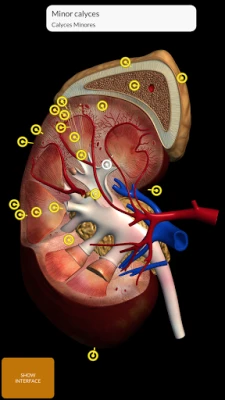

"Anatomy 3D Atlas" allows you to study human anatomy in an easy and interactive way.

Through a simple and intuitive interface it is possible to observe every anatomical structure from any angle.

The anatomical 3D models are particularly detailed and with textures up to 4k resolution.

The subdivision by regions and the predefined views facilitate the observation and the study of single parts or groups of systems and the relationships between different organs.

ANATOMICAL 3D MODELS

• Urogenital system (male and female)

"Anatomy 3D Atlas" allows you to study human anatomy in an easy and interactive way.

Through a simple and intuitive interface it is possible to observe every anatomical structure from any angle.

The anatomical 3D models are particularly detailed and with textures up to 4k resolution.

The subdivision by regions and the predefined views facilitate the observation and the study of single parts or groups of systems and the relationships between different organs.